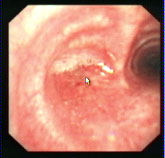

主持人:继续看这段采访。经过确诊女患者小陆已经是左肺全肺不张,这时医生建议她做手术切除左肺。 李强:患者刚到我院时情况确实很严重,从当时的X光片中可以看到患者的左肺已经是完全不张了,而且由于左肺的不张气管被严重的牵拉到左侧,另外从支气管镜片中可以看到整个左主支气管已经完全被结核病灶所闭塞了,因此病人稍微一活动就会觉得呼吸困难。最后完全堵住就会形成肺不张。

主持人:内镜治疗到底是如何进行的? 李强:如图通过支气管镜可以很容易看到病变部位,可以通过球囊扩张进行治疗,球囊通过支气管镜进入病变支气管,然后通过注水使球囊的压力增高,把狭窄的支气管扩开。另一个画面上显示的是一个病变的支气管,有很多疤痕的增生,特别是在支气管的下端已经形成了明显的狭窄,这时采用支气管内镜把球囊导入到病变部位的支气管,经过导管往球囊内注水后可以达到5-6个大气压,就可以把支气管扩开了。如图我们经过几次疏通后患者上叶的支气管已经疏通了,经过多次努力全肺的支气管都得到了疏通,最后再进行完球囊扩张和支架植入后患者的呼吸已经和正常人一样了。 白冲:内镜的诊断和治疗特点可以归纳为以下几点1、大大提高了支气管结核的诊断准确率。2、内镜下的诊断和治疗手段是非常丰富的,在各个时期都可以进行。3、比传统手术创伤小得多,尽大可能保证了病人的肺组织,大大提高了病人的生活质量。